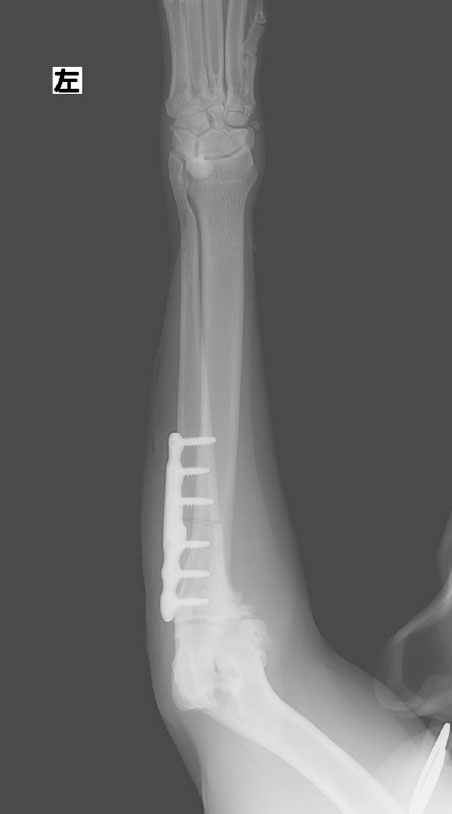

近位尺骨外反骨切り術

前肢尺骨を骨切りして角度を矯正、荷重バランスを均等に。

PAUL法では尺骨を特殊な角度で骨切りし、肘関節の内側と外側に均等に荷重がかかるよう、専用の金属板と骨ネジで固定して角度矯正を行います。軟骨は一度消失すると再生されないので、外側の軟骨に損傷が起こる前に手術を行う必要があります。